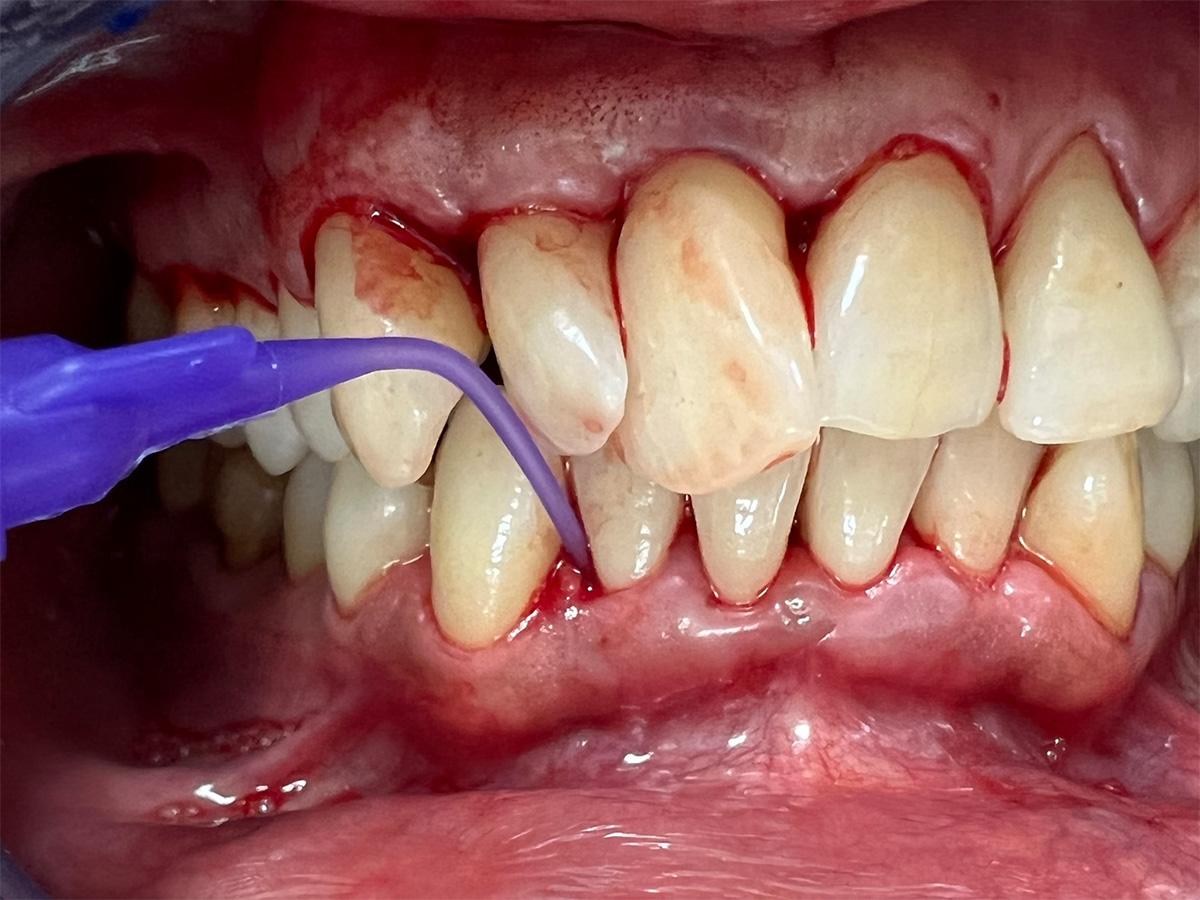

In diesem Workshop erhalten Sie umfassendes Wissen für die Behandlung von Parodontitis-Patientenen. Zunächst führt Sie Yvonne Gebhardt durch moderne subgingivale Behandlungskonzepte – das Herzstück der PA-Therapie. Anschließend erklärt Ihnen Sonja Steinert die faszinierenden Zusammenhänge des Knochenstoffwechsels: Wie Entzündungen den Knochenabbau fördern und wie Sie mit gezielter Therapie und Vitamin D gegensteuern können.

• Subgingivales Behandlungskonzept

• Parodontale Krankheitsbilder erkennen